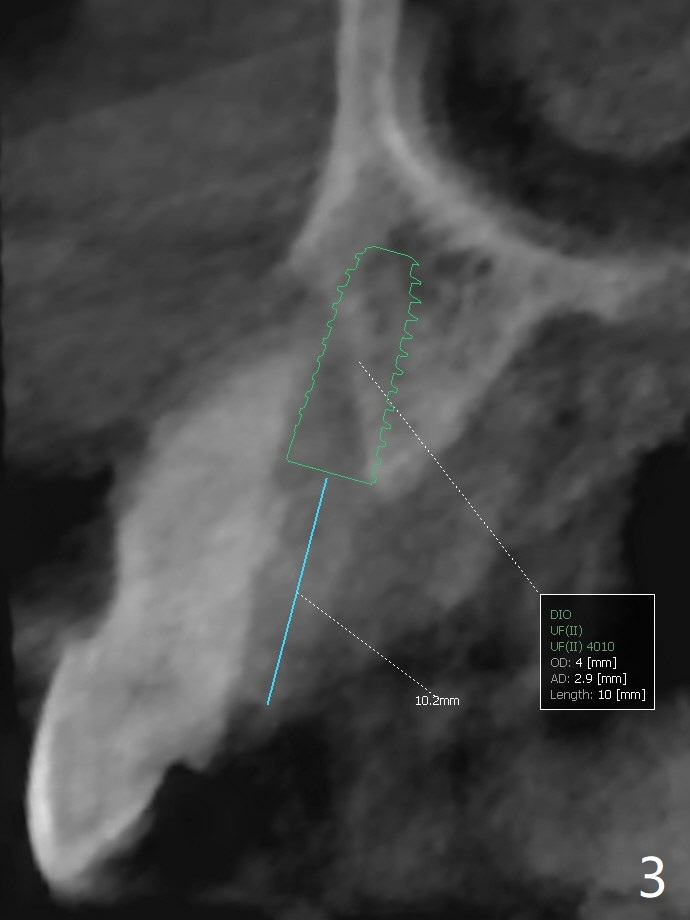

A 62-year-old man with generalized chronic periodontitis returns with chief complaint of loose tooth at #11 (Fig.1). Although a buccal fistula (Fig.1 <) is closer to #12 than to #11, percussion is more severe at #11 than 12. The buccal plate of #11 is missing, but it is possible to place a narrow immediate implant because of the wide alveolus (Fig.2). Since the gingiva is ~ 10 mm long, a mill abutment is to be used (Fig.3,5). In fact the fistula communicates with #11 extraction socket. After debridement, osteotomy is initiated (Fig.4) for a 3.8x10 mm implant ~ 35 Ncm, followed by seating a 4.5x2 mm mill abutment (Fig.5). Abundant sticky bone is placed in the remaining socket (for buccal plate reconstruction) and against the root surface of the neighboring teeth (Fig. 6 * (#10,12)). Finally 2 pieces of PRF membranes are utilized to facilitate repair of the buccal soft tissue defect (Fig.7 *). The root prominence of the canine seems to be maintained by the bone graft (Fig.8 C). Acrylic dressing holding the PRF membranes in place remains in situ with the healthy gingiva buccal (Fig.9) and palatal (Fig.10) 11 days postop. Note the acrylic locking into the undercuts of the neighboring teeth (*). 经过一段摸索发现离心每分钟1500转5分钟后,抽取上清液,接着再离心10分钟剩余上清液就形成血小板块,压制后便是血小板膜,后者似乎有助于软组织愈合,而上清液用来制备骨块,帮助硬组织生长。利用这个原则讨论以下病例治疗。The gingival margin gains ~ 5 mm 6 weeks postop when the acrylic dressing is removed (Fig.11,12 (<: previous one), as compared to Fig.7,8). 治疗结束时尖牙牙龈缘高于第一双尖牙(图七,八),六个星期后,尖牙牙龈缘却低于双尖牙(图十一,十二(箭头:原始牙龈缘))。术后2.5,4.5月基台周围牙龈似乎能与钛合金附着,防止细菌进入深部植体(图十三,十四)。临时牙冠脱落多次,可能与mill abutment太光滑有关,所以颊侧,舌侧磨成平面(图十四)。取模时好像不必取出基台清洗(仿佛没有炎症),原位用树脂延长基台。术后5个月CT显示颊侧骨板再生(图十六-十八)。取模时并没有用树脂加长基台;粘固时,牙冠颜色理想,但是照片中并不是如此(图十九,二十),颊侧骨板没有塌陷。术后11个月基台颊侧骨板没有萎缩(图二十一:B);3d图像:骨壁完全形成(图十六对比:部分形成)。密度也增高(图二十二:B),与术后五个月比较(图十七)。术后十一个月,粘固后五个月角化龈存在(图二十三),牙冠颈部有金属颜色透出,是因为二段式基台太粗了(最细4.5毫米),可以请实验室在牙冠内部涂opaque material而减轻。